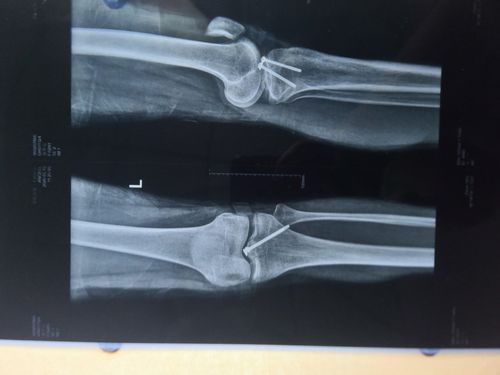

膝关节髁间棘骨折图片

膝关节髁间棘骨折图片,胫骨髁间骨折图片

胫骨髁间棘撕脱骨折.ppt

髁间棘后交叉韧带撕脱骨折内侧副韧带撕裂关节镜微创治疗

关节镜下髁间棘骨折内固定

胫骨髁间棘撕脱骨折

胫骨髁间棘骨折图片

胫骨髁间棘图片

胫骨髁间棘

髁间嵴骨折